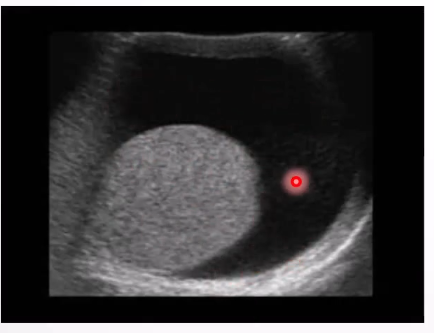

Hydrocele: A serous fluid collection between layers of the tunica vaginalis surrounding the testis or spermatic cord.

Ultrasound Appearance: Testicular

Simple avascular fluid collection around the testis, may extend to the inguinal canal

Low-level echoes possible due to protein aggregation or cholesterol crystals.